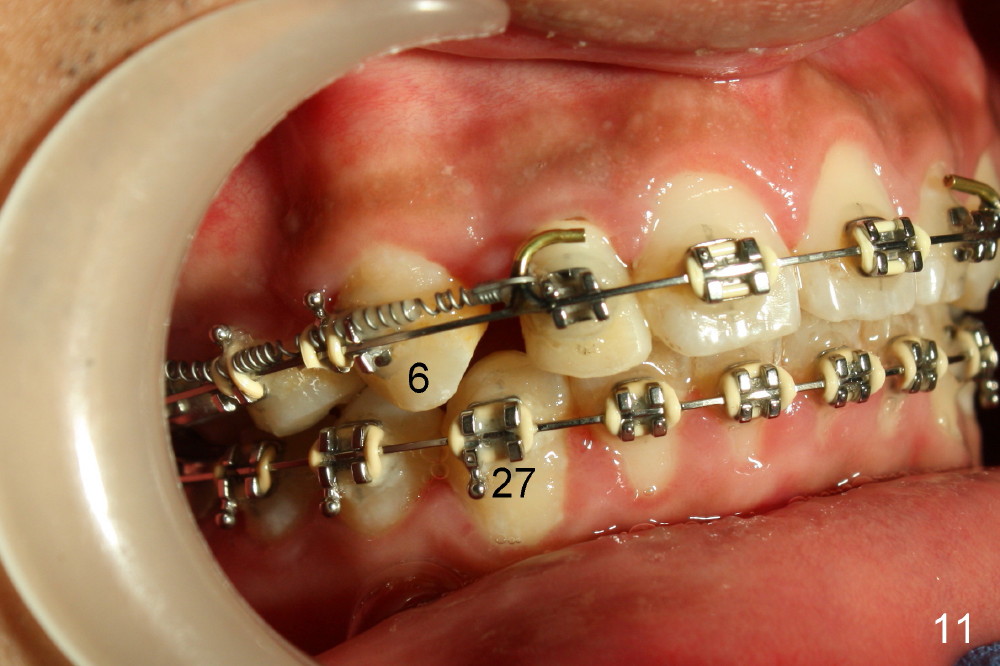

The patient returns 1 month post distalization of the upper incisors (Fig.10-12, 9 months of treatment). Bilateral canine relationship is Class I (Fig.11,12). All needs to be done is to continue distalizing the upper incisors or slightly mesialize the canines if indicated.